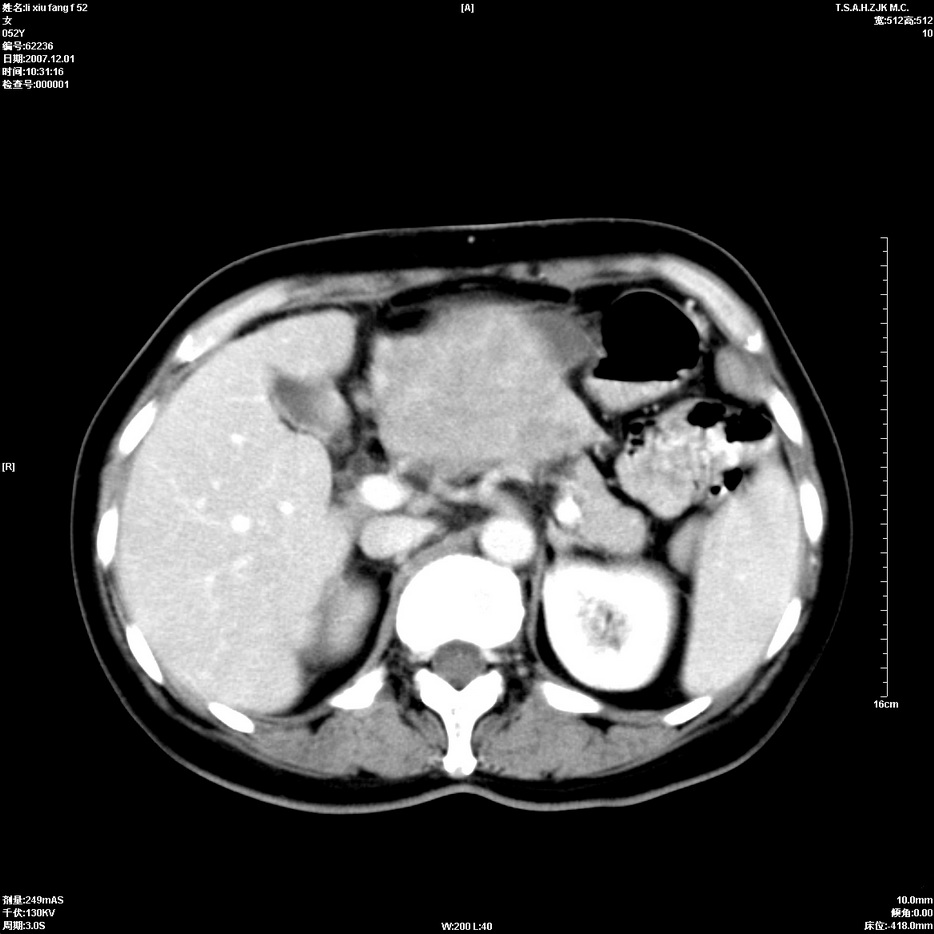

标题: CT12858:女,52岁,胎甲球蛋白861肝左叶占位,肝癌。下腔静 [打印本页]

标题: CT12858:女,52岁,胎甲球蛋白861肝左叶占位,肝癌。下腔静

肝左叶巨大低密度灶肿块,增强符合快进快出表现,有动静脉交通支;静脉期,下腔静脉内有充盈缺损,afp明显升高,支持肝癌并下腔静脉癌栓形成。

支持楼主   门静脉主干及左支癌栓形成

以下是引用拾荒者在2008-4-15 22:57:00的发言:[br]肝左叶巨大低密度灶肿块,增强符合快进快出表现,有动静脉交通支;静脉期,下腔静脉内有充盈缺损,afp明显升高,支持肝癌并下腔静脉癌栓形成。